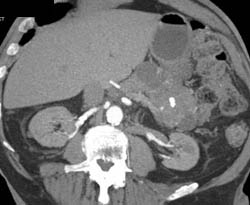

Chronic Pancreatitis